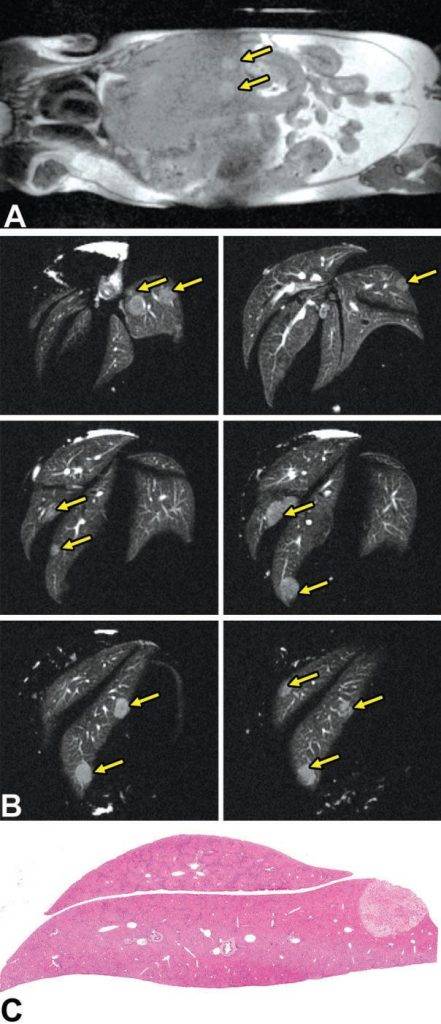

活體磁共振成像在模型小鼠中檢測到局灶性肝損傷(圖A)。肝臟的高分辨率離體MRH評估可以在小鼠(圖B和C)中鑒定幾個單獨的局灶性脂肪病變。通過常規組織病理學證實病變為局灶性脂肪改變(圖C)。